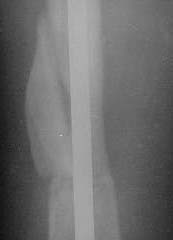

THX for all suggestions and wonderful clinical cases. I just performed closed nailing with static locking. Images attached. We still haven't yet availavble thick locking bolts so use 4,5 cortical screws instead so i don't plan to hurry with weight bearing. Comments are welcome.